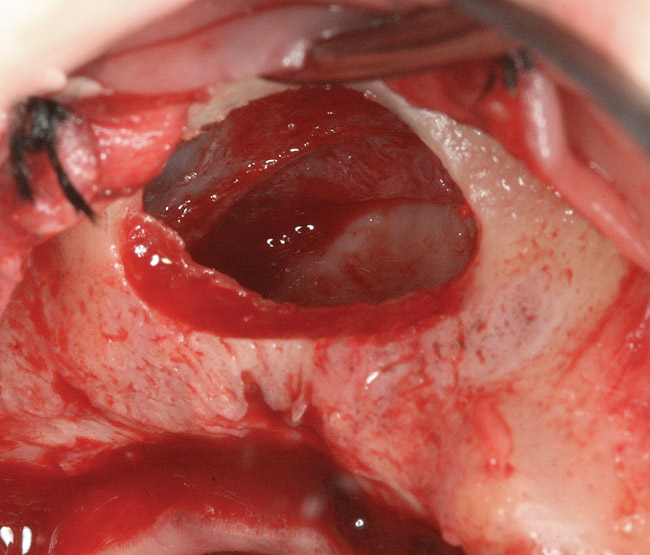

Fig 3. Schneiderian membrane from the sinus walls is elevated.

Figure 3